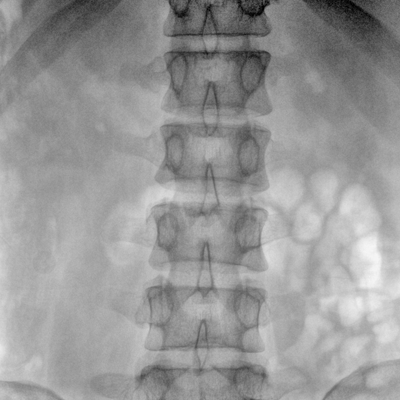

大尺寸動態平板探測器,高DQE、低噪聲、圖像清晰。采用多分辨率圖像增強處理技術,不同部位不同圖像處理算法,滿足客戶多樣化的需求。

采用智能變頻脈沖透視技術,優化圖像質量的同時降低輻射劑量,呵護醫患健康